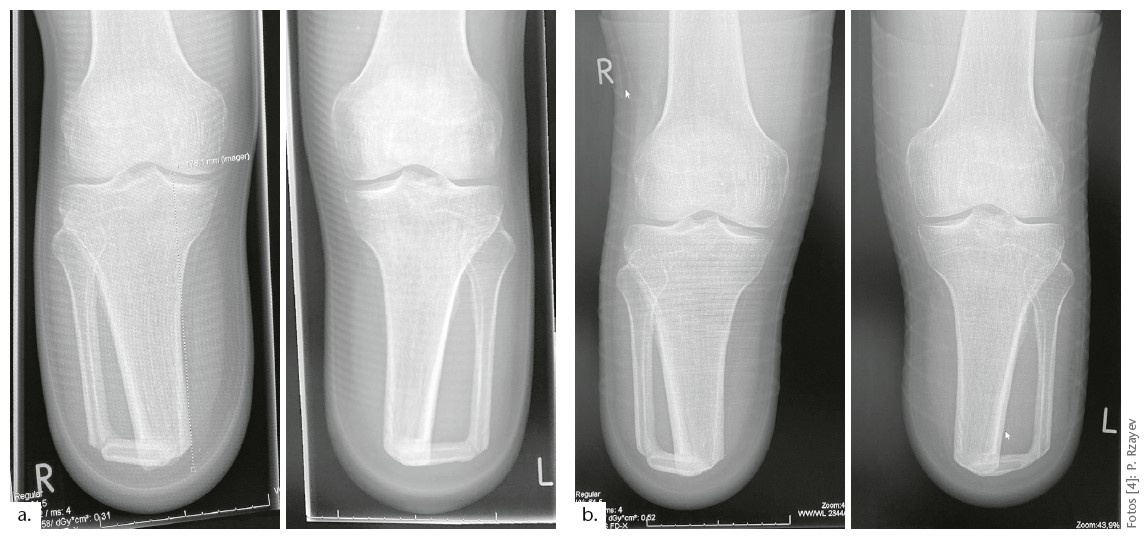

Status der Brückensynostose nach 24 Monaten

Hochinteressant ist, welche Umbauprozesse sich an der Tibiaspitze und der Fibulastrebe vollzogen haben. Am auffälligsten ist das an der linken Brückensynostose erkennbar: Überflüssige knöcherne Randbereiche werden durch Demineralisierung abgebaut. Ein besonderes Monitoring ist daher nicht erforderlich. Jeder vitale Knochen behält nur die Dimension, die für seine stabilisierende Funktion notwendig ist. Das linke Bein ist weiterhin Stand- und Stopp-Bein geblieben.

Die linke und rechte Brückensynostose sind geometrisch nicht identisch. Am linken Stumpf trifft die Fibulastrebe in transversaler Betrachtung (von distal) nicht im gleichen Winkel auf die mediale Tibiafläche. Diese Modifizierung ist bisher ohne spürbare Auswirkung (Abb. 12).